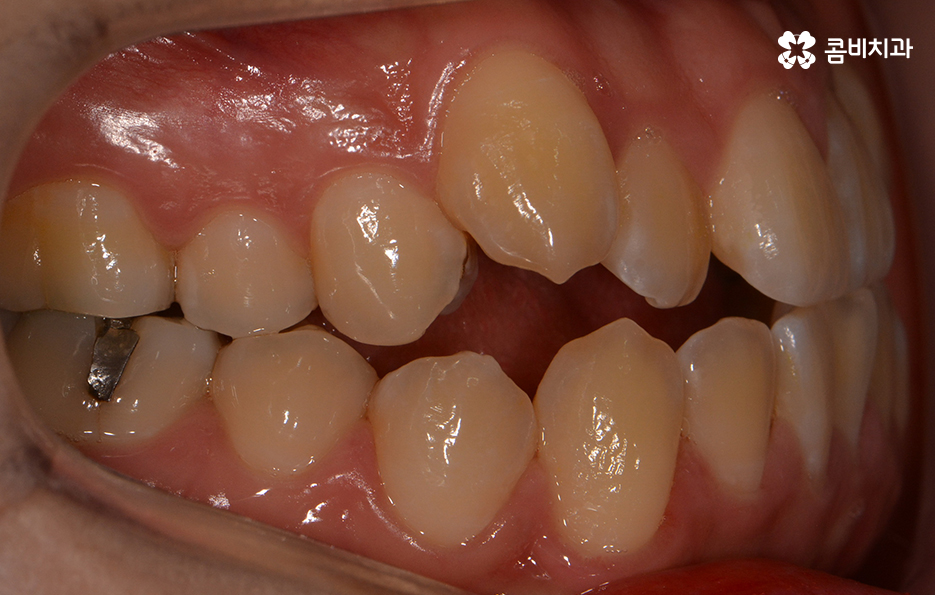

위 환자분의 경우에는 비발치로 송곳니 덧니 교정이

진행된 사례이며 전체 진료 기간은 약 1년 6개월가량이 소요되었습니다.

송곳니 덧니 치료를 할 때 주의해야 할 점은

자신의 골격과 얼굴형을 충분히 생각해야 한다는 것입니다.

덧니 자체만 본다면 비교적 심하지 않은 분들도

계실 수 있겠지만 치아가 돌출되어 있으신 경우에는

옆모습이 돌출입으로 보일 수 있기 때문에